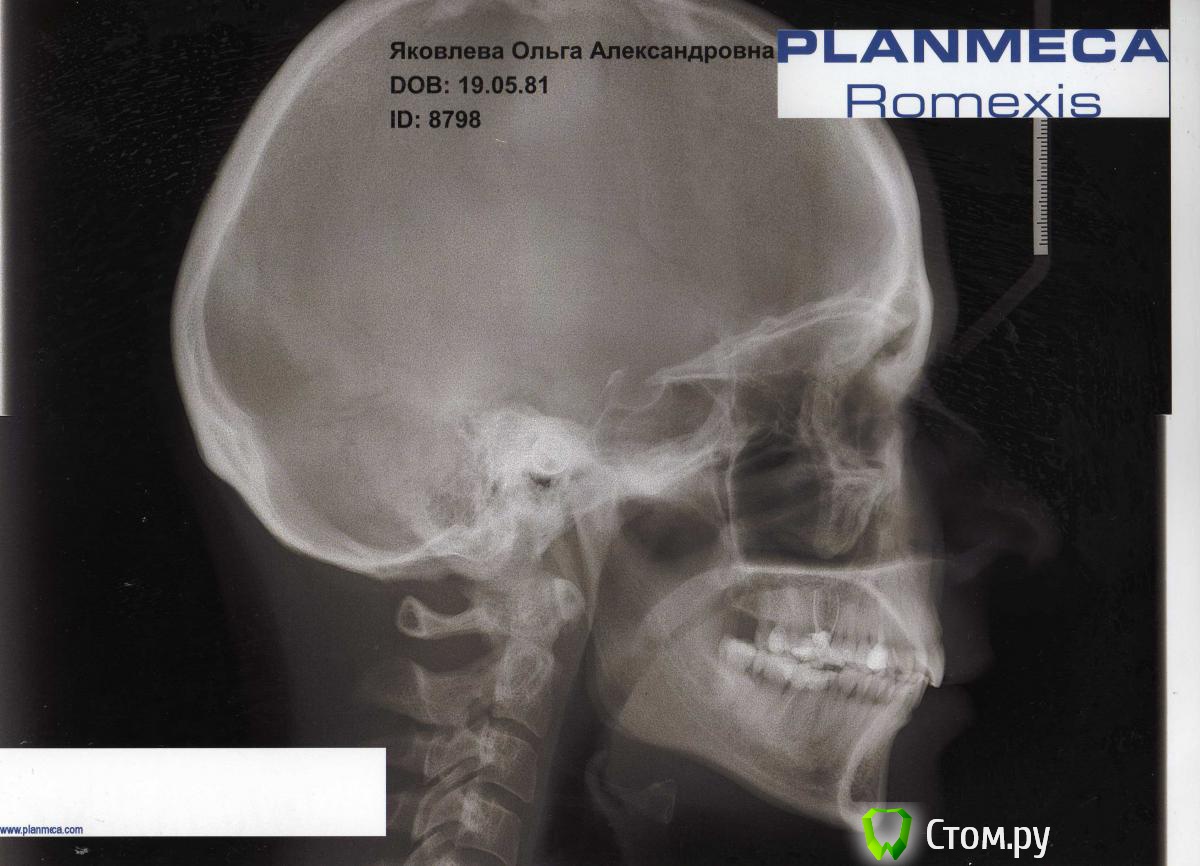

ОлиЯ Опубликовано 13 февраля, 2014 Автор Поделиться Опубликовано 13 февраля, 2014 это четверть данных(учитывая качестов снимка-1/10) теперь фото и ТРГ))доктор как вы сказали. все сделала))) Ссылка на комментарий

Ayrat_zub Опубликовано 13 февраля, 2014 Поделиться Опубликовано 13 февраля, 2014 (изменено) доктор как вы сказали. все сделала)))гораздо лучше))) оптг вверх ногами вопрос только как будут закрывать промежутки, , - 1- на верхней челюсти, там где нет 6-ки, 7-ка просто "наклонилась вперед", необходимо ее выровнять, и если не планируется имплантация 6-ки, то закрыть промежуток корпусно, сдвинув 7-ку 6-ку вперед,2-на нижней челюсти 6-ки правда с сомнительным прогнозом, терапевты лучше скажут, если их убирать без имплантации, то так же, нужно закрывать промежутки, корпусно двигая 7-ки и 8-ые зубы)скорее всего понадобиться немало времени+ жевательная поверхность 7-ок несколько различается от 6-ок, необходимо будет сделать реставрацию по окончании перемещения) детальнее план только с моделями и фото на очной консультации можно построить)верхняя 6-ка -тоже не очень, отпишитесь в раздел "терапии") Изменено 13 февраля, 2014 пользователем Ayrat_zub Ссылка на комментарий